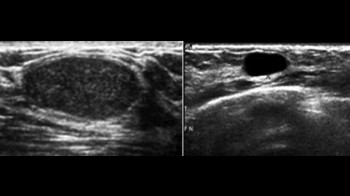

- Mamografiju i/ili ultrazvuk dojki

Šta je mamografija?

Mamografija je snimanje grudi sa niskom dozom rtg zracenja u cilju ranog otkrivanja karcinoma dojke koji je kod zena prvi po ucestalosti medju karcinomima. Preporucuje se uraditi je jednom godišnje, iza 40-te godine zivota, a ultrazvuk dojki do 40-te godine. Pregled takodjer treba uraditi ako osjetite tvrdo tkivo ili žlijezdu u grudima, iscjedak iz bradavice ili ako imate pozitivnu porodicnu anamnezu karcinoma dojke.

U 5-15% mamografskih snimaka naći ce se promjena koja zahtijeva dodatni pregled, kao ultrazvuk grudi, biopsiju ili kontrolnu mamografiju.